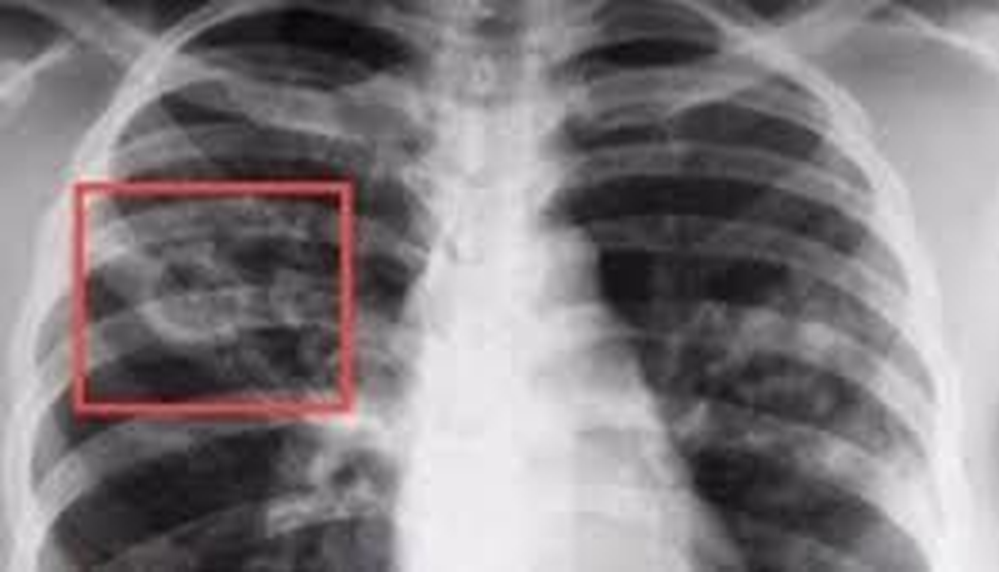

Художественное изображение рентгенограммы легких при туберкулезе.

Рисунок 3. Как враг выглядит в лицо.

Итак, Кох дал врагу имя, а Рентген — сделал его уязвимым, позволив засекать его диверсии в режиме реального времени. Человечество, наконец, вооружилось для настоящей войны, которая переходила из области мистики и романтических мифов в область точной науки. Это раз и навсегда поменяло отношение общества к туберкулезу. Его мистический флер был развенчан навсегда.